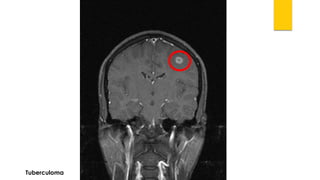

Tuberculoma